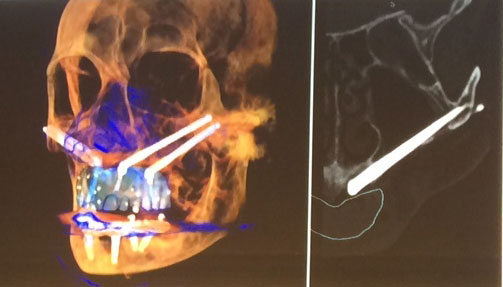

Placement Of Zygomatic Implants For Severe Bone Atrophy Of Maxillary Bone

Zygomatic implants are an alternative for patients who do not have much bone left in the upper jaw, or for patients missing most or all of their teeth. The surgery is done for the upper jaw where bone conditions have insufficient anchorage for a prosthesis. The implants are longer than ordinary dental implants so that they can anchor to the bone that forms the cheekbone (zygomatic arch). It only takes one surgical procedure, minimal surgical trauma and treatment time, and does not require any bone grafts.